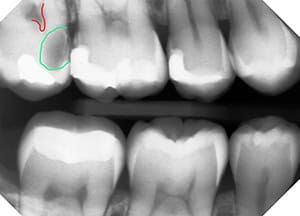

Here’s the starting x-ray, taken on Dec. 14, 2014 . If you look at the circled area, it looks fairly normal. Unfortunately, there was a slight overlap of the teeth in the x-ray, as the digital sensor was angled ever-so-slightly, and the overlap may have masked the area of concern, preventing an earlier diagnosis. Since the patient had few fillings, though, indicated a low risk of cavities overall, we didn’t retake the x-ray to avoid unnecessary exposure. Nevertheless, there’s really nothing there that caused me any concern.

Check out the circled area this time, eh? I’ve outlined the nerve chamber in the tooth on the x-ray in red and the cavity in green, but it’s important to know that a cavity is never sharply defined like this. There are several zones identifiable in cavities, highlighted in the next image. We also know that cavities are typically about 20-30% bigger than can be seen on an x-ray, which is due to 2 reasons:

- The deepest zone of decay has not yet softened enough to be less dense enough for x-rays to detect it, as dental x-rays are all about levels of density. Darker black areas mean it’s extremely soft and x-rays go right through without being blocked, while bright white areas indicate that x-rays are being completely stopped.